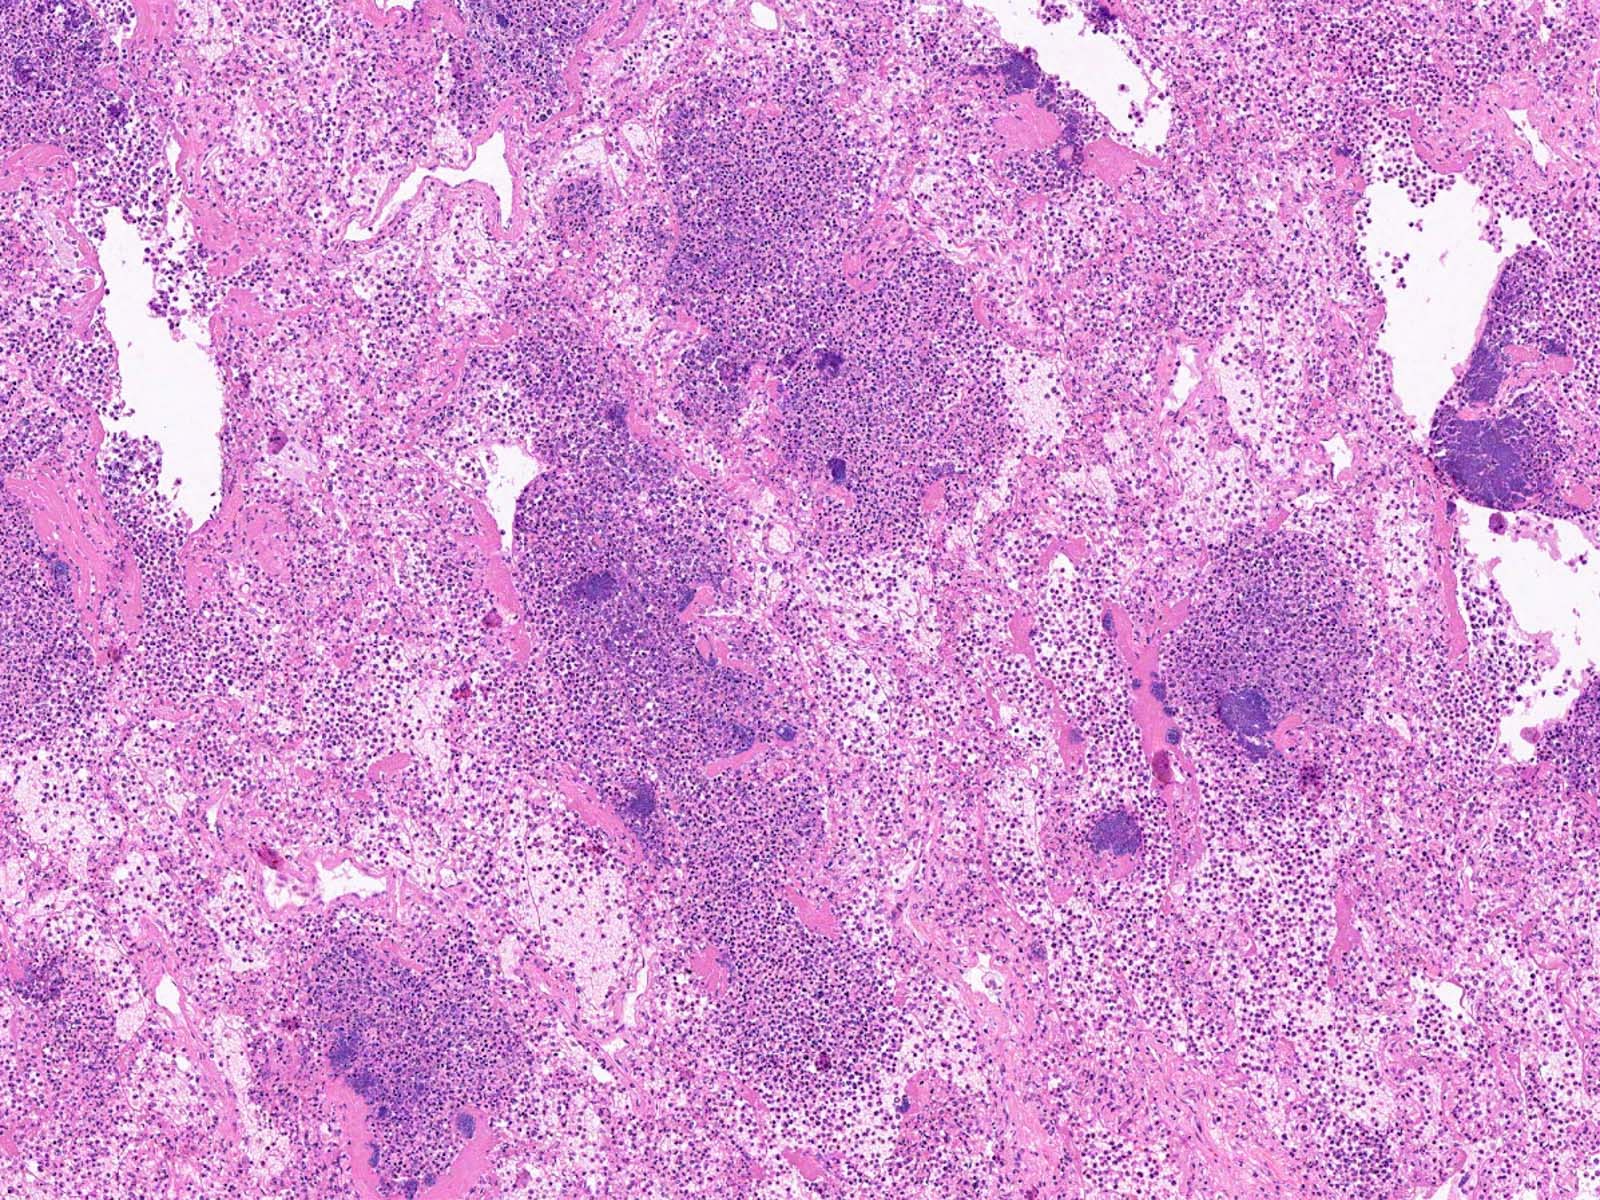

Microscopic (histologic) description

- Lobar pneumonia (Semin Diagn Pathol 2017;34:498):

- Uniform inflammatory infiltrate, the changes are at the same stage throughout the entire lobe

- Early stage: vascular engorgement, intra-alveolar fluid with few neutrophils and often bacterial colonies

- Massive confluent exudate with intra-alveolar neutrophils, red cells and fibrin, correlates with red hepatization on gross exam

- Progressive disintegration of red cells and the persistence of a fibrinosuppurative exudate, correlates with gray hepatization on gross exam

- Resolution phase: exudates converted to fibromyxoid masses rich in macrophages and fibroblasts

- Usually resolves with minimal fibrosis

Microscopic (histologic) images

- Microscopic description

- Lungs: Sections of the lungs show intra-alveolar neutrophilic infiltrate with marked congestion. Alveolar septa are widened with mixed inflammatory cells. Reactive pneumocytes and hyaline membrane can be seen throughout the lung tissue.